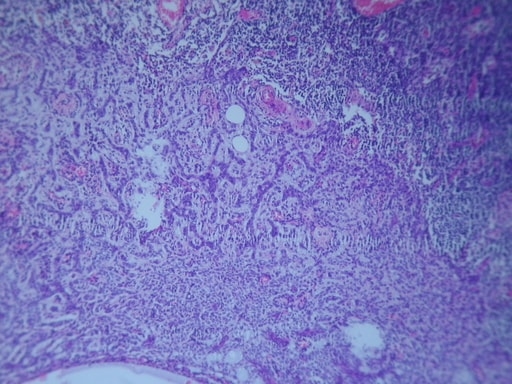

CARCINOMA MUCOSO